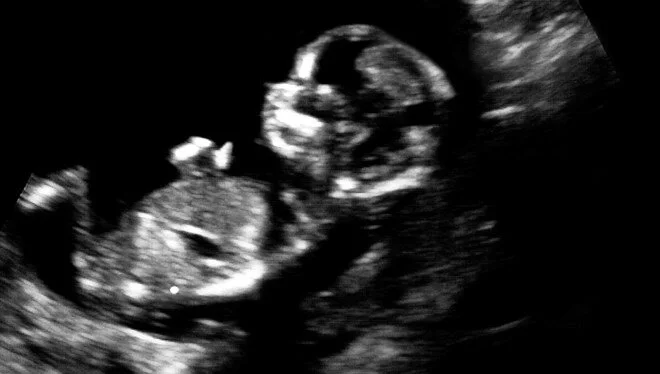

Anne karnındaki bebek kalp ameliyatı oldu -